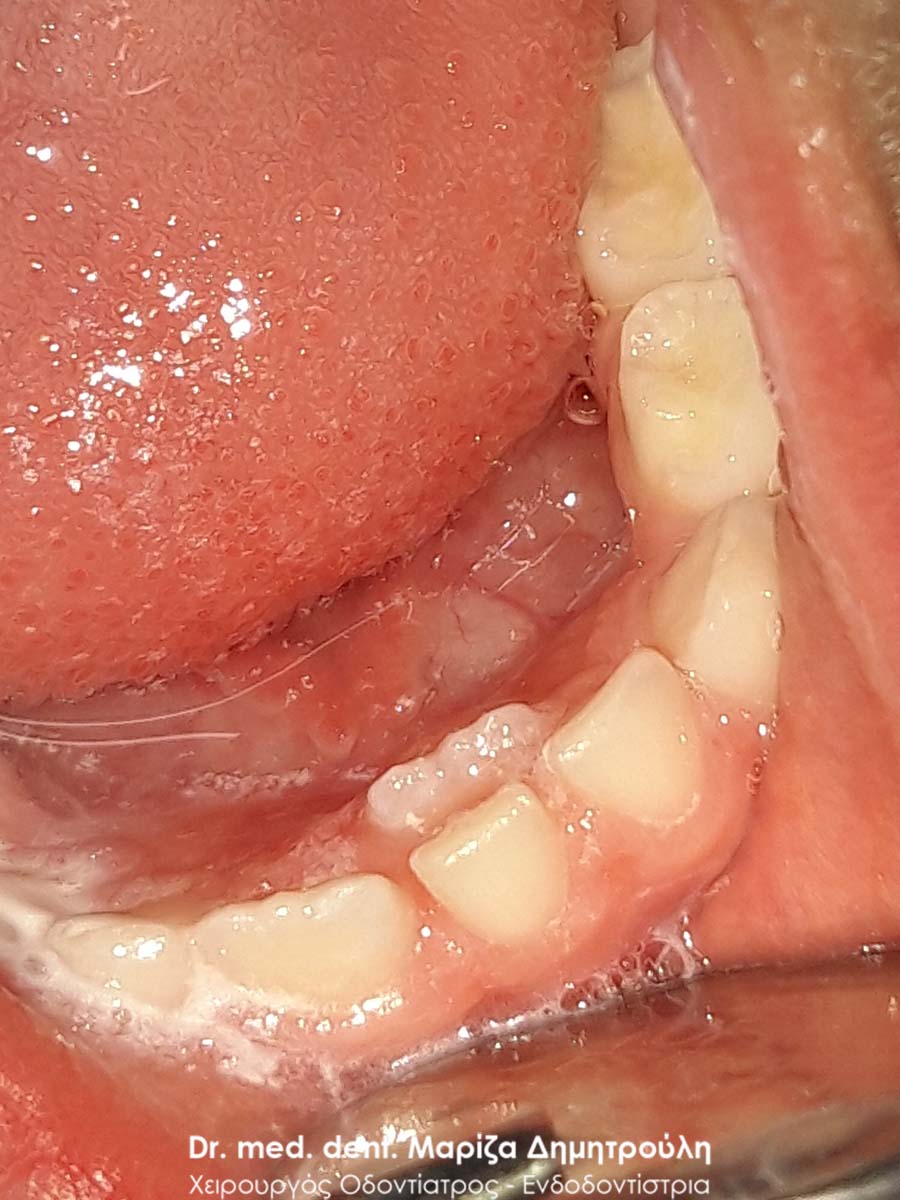

BEFORE

AFTER

Extraction of double primary tooth